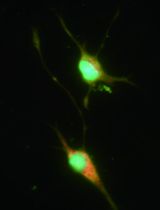

Figure 1. Expression of laminin chains in the limbal stem cell niche in situ. A. Quantitative real-time polymerase chain reaction (qRT-PCR) primer assays showing higher expression levels of laminin α2 (LAMA2), α4 (LAMA4), α5 (LAMA5), β2 (LAMB2), β3 (LAMB3), and γ2 (LAMC2) in microdissected limbal epithelial stem/progenitor cell (LEPC) clusters compared with basal corneal epithelial cell (BCEC) populations; laminin α1 (LAMA1), α3 (LAMA3), β1 (LAMB1), β4 (LAMB4), γ1 (LAMC1) showed no differential expression patterns. B. Immunofluorescence analyses of corneoscleral tissue sections showing differential staining patterns of laminin α2, α5, β2, β3, γ2, and γ3, but similar staining patterns of laminin α1, α3, β1, and γ1 in the basement membranes of corneal and limbal epithelia; laminin α4 was largely negative in epithelial basement membranes. C. Immunofluorescence double labeling of laminin (LN) α5 (green) and cytokeratin (CK)15, N-Cadherin, p63α, integrin α6, integrin α3, and integrin β1 (red); nuclear counterstaining with DAPI (blue); scale bar = 20 µm. Reprinted from Polisetti et al., 2017, licensed under a CC BY 4.0.